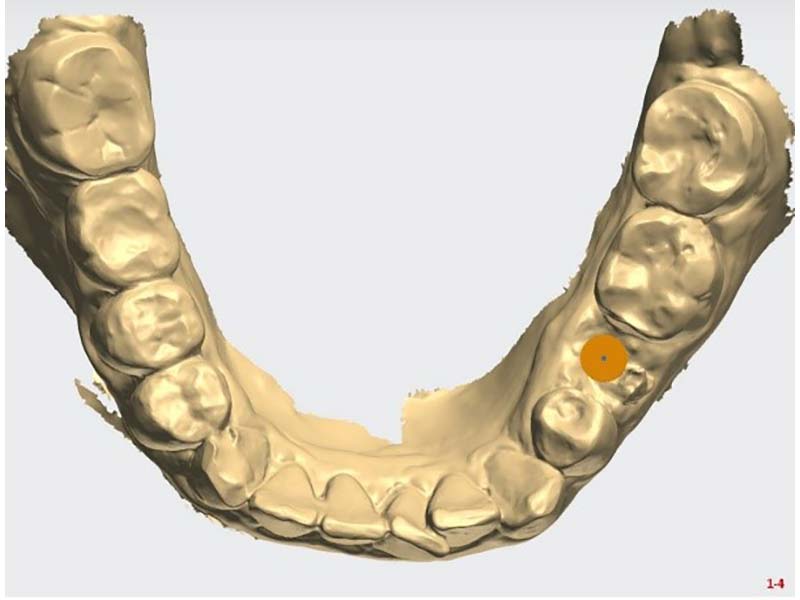

拍攝電腦斷層影像和口腔口掃並製作治療計畫

植牙案例分享